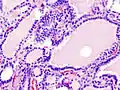

Hyperthyroidism is one of the most common endocrine conditions affecting older domesticated housecats. In the United States, up to 10% of cats over ten years old have hyperthyroidism.[45] The disease has become significantly more common since the first reports of feline hyperthyroidism in the 1970s. The most common cause of hyperthyroidism in cats is the presence of benign tumors called adenomas. 98% of cases are caused by the presence of an adenoma,[46] but the reason these cats develop such tumors continues to be studied.

The most common presenting symptoms are: rapid weight loss, tachycardia (rapid heart rate), vomiting, diarrhea, increased consumption of fluids (polydipsia), polyphasia, and increased urine production (polyuria). Other symptoms include hyperactivity, possible aggression, an unkempt appearance, and large, thick claws. Heart murmurs and a gallop rhythm can develop due to secondary hypertrophic cardiomyopathy. About 70% of afflicted cats also have enlarged thyroid glands (goiter). 10% of cats exhibit "apathetic hyperthyroidism", which is characterized by anorexia and lethargy.[47]